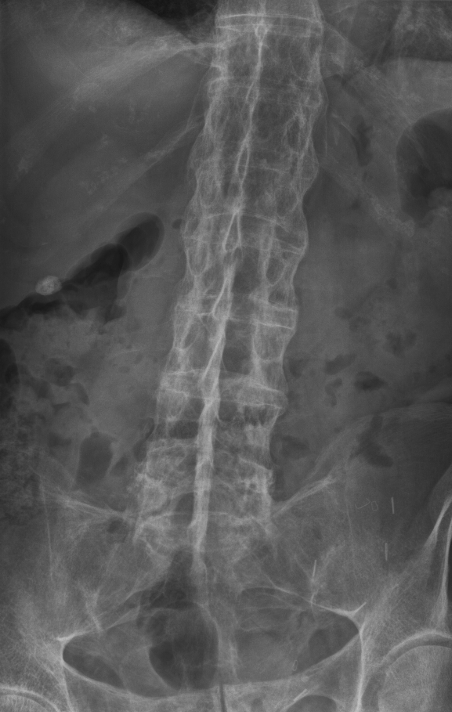

Ankylosing Spondylitis (AS)

26M with back stiffness and general malaise. Lumbar AP radiographs below. Diagnosis?

@Jenmatos0 @Neuromed_ @BrownJHM @Lap_surgeon @drkeithsiau Ankylosing Spondylitis 🌐inflammation of articulations and vertebrae cause tenderness 🌐exercise may improve pain 🌐shoulders, feet and knees may be affected too 🌐HLA-B27 is the haplotype ⬆️CRP and ESR 🌐exercise and prevention of spinal complications are key for treatment ✅